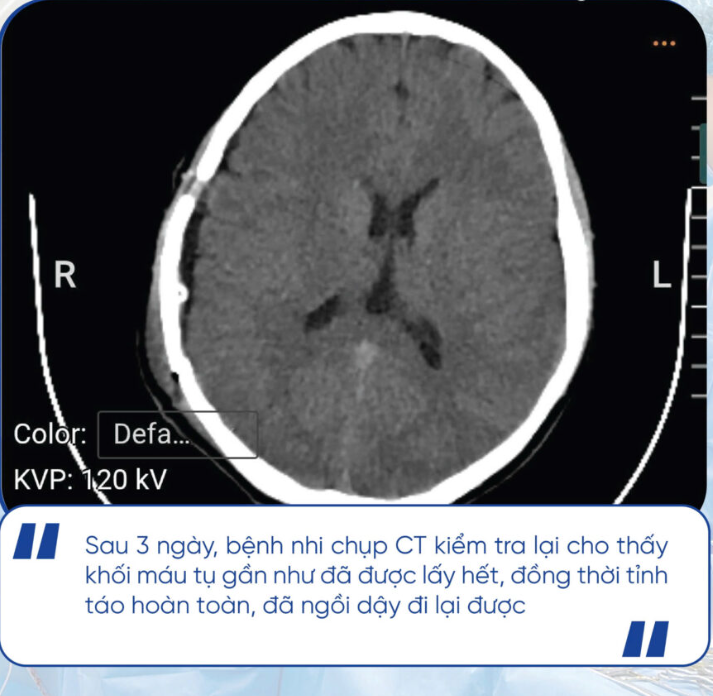

Sau phẫu thuật, bệnh nhi dần ổn định. Sau 3 ngày, bệnh nhi chụp CT kiểm tra lại cho thấy khối máu tụ gần như đã được lấy hết, đồng thời tỉnh táo hoàn toàn, đã ngồi dậy đi lại được. Đến ngày thứ 7, bệnh nhi đã được ra viện.